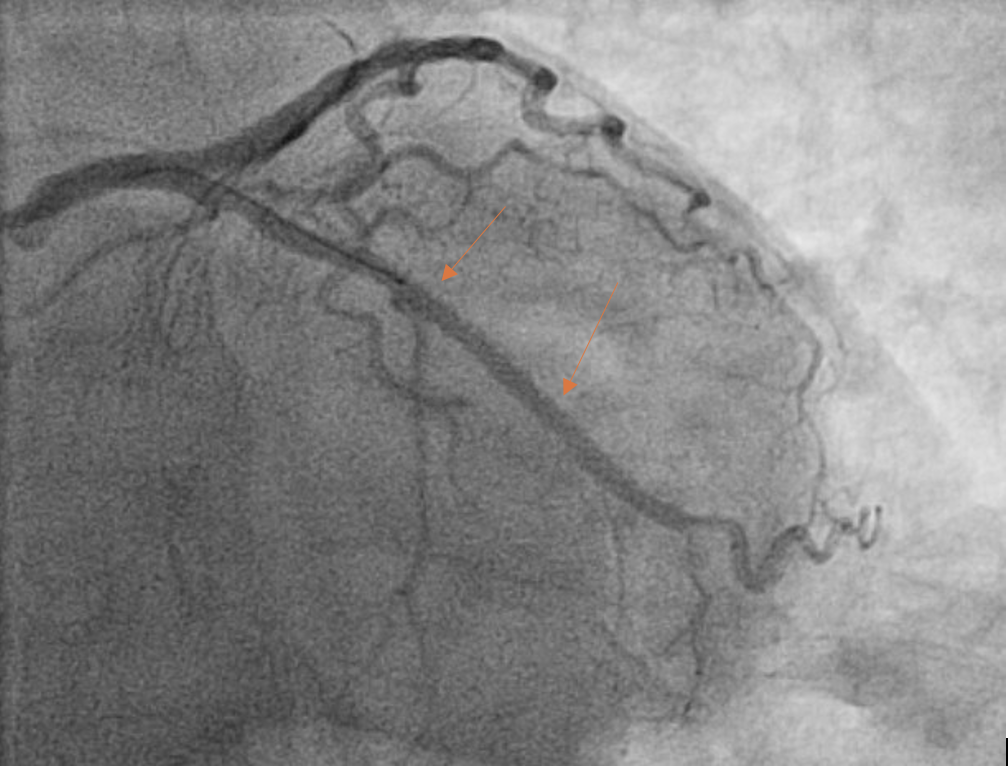

The pre-PCI angiogram reveals complete occlusion of left circumflex (LCx) artery.